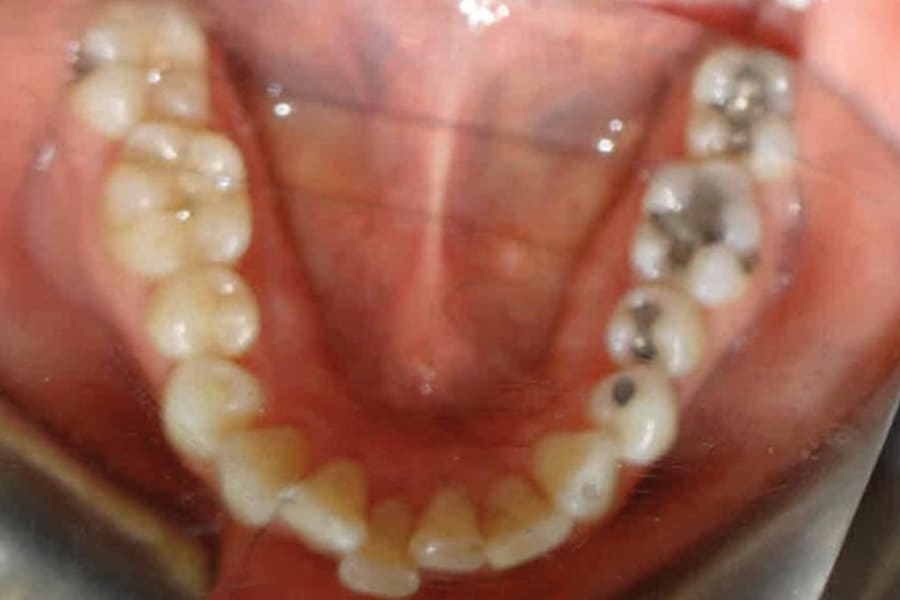

A 35-year-old woman presented with concerns of crowding, bruxism, and bite misalignment, which were associated with a class II malocclusion that would require a combination treatment of expansion, distalization, and molar derotation. ClearCorrect® aligner therapy (Straumann, clearcorrect.com) was selected as the primary modality, as the patient requested a non-invasive, esthetic treatment. The treatment plan was designed to be completed within 6 months of active aligner therapy. Class II elastics were prescribed, and the ClearCorrect FLEX case plan was chosen to allow for refinements, as needed. After comprehensive digital records were taken, the first set of aligners was delivered, engagers were bonded, and the patient was instructed to wear aligners on a 14-day cycle with full-time class II elastic wear. To enhance efficiency, more engagers were placed, including posterior attachments, to maximize control over molar distalization and anchorage. Interproximal reduction of 0.3 mm was performed in a few contacts at the initial appointment to facilitate space closure and alignment. Due to the complexity of the correction and the patient’s history of bruxism, a lower 3-3 bonded retainer was placed, and retainers were fabricated for both arches. The patient expressed a high level of satisfaction with the ClearCorrect aligner therapy, noting the comfort and esthetics of the aligners and the ability to achieve a fully corrected class II occlusion in just 6 months of treatment.